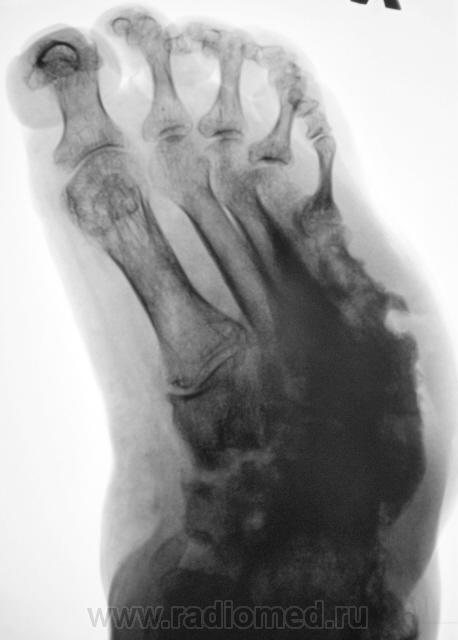

Одна стопа.

[[wysiwyg_imageupload:775:]][[wysiwyg_imageupload:776:]][[wysiwyg_imageupload:777:]]

Хронология с 1997 года.

Так все-таки, изменения в 5 плюсневых первично-диабетичны (такого не описывают в учебниках), или per contuitatem от язв?